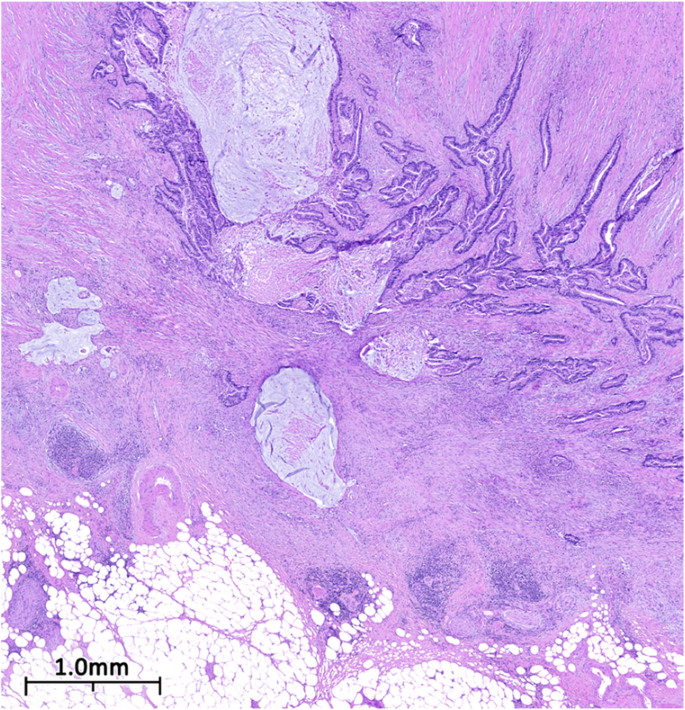

The patient then underwent a laparoscopic appendectomy, where an abundance of mucin was observed. This was followed by a right hemicolectomy, partial omentectomy, and lymph node dissection. Microscopic examination of the appendix revealed a mucinous adenocarcinoma that had invaded through the muscularis propria into the subserosa without lymphovascular invasion. The tumor was staged as pT3b pN0 M0 G2 (Figs. 2 and 3). After discharge, the patient was referred to oncology and FOLFOX regimen (levoleucovorin, fluorouracil, and oxaliplatin) was recommended.

Low power photomicrograph of dissected appendiceal tissue. Figure 2. Low power photomicrograph of H&E stain showing moderately differentiated branching neoplastic glands focally distended by mucinous material and invading the muscularis. Mucinous pools partially lined with neoplastic epithelium are also present

High power photomicrograph of dissected appendiceal tissue. Figure 3. High power photomicrograph of H&E stain showing moderately differentiated neoplastic glands lined by cells with nuclear pleomorphism and hyperchromasia (Hematoxylin and Eosin)